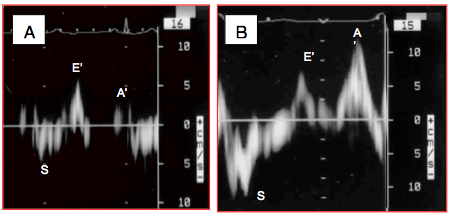

Le premier pas de l’évaluation fonctionnelle est un examen global du cœur en 4-cavités (vue mi-œsophage 0-20°), car celle-ci fournit le cadre général dans lequel vont s’inscrire les différents indices mesurés. Il permet de relever la taille respective des chambres cardiaques, leurs relations, leur dilatation et leur éventuelle hypertrophie. Cette vue générale est capitale pour intégrer les calculs détaillés qui n'expriment qu'une vue partielle de la réalité. Tout résultat ultérieur doit être compatible avec la silhouette fonctionnelle des cavités et des gros vaisseaux. L'image 4-cavités permet aussi quelques observations intéressantes (Figure 25.170).

Figure 25.170 : Vues 4-cavités 0° pour l'évaluation visuelle de la fonction du VG. A: cœur normal; la paroi du VG est musclée, la taille du VG et de l'OG est normale, la zone apicale apparaît pointue, la fraction d'éjection est 0.7. B: insuffisance chronique du VG; le ventricule est dilaté, sa paroi amincie, la zone apicale est arrondie, le débattement du feuillet antérieur de la mitrale est faible (flèche verte). C: lorsque la fonction du VG est normale, le débattement du feuillet mitral antérieur est ample; le feuillet est presque parallèle au septum en diastole. D: insuffisance mitrale restrictive sur dysfonction et dilatation du VG; les feuillets sont retenus en-dessous du plan de l'anneau mitral en systole (trait pointillé blanc) et la valve fuit.